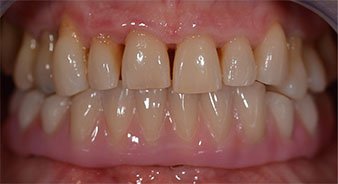

La patiente âgée de 64 ans présente une denture résiduelle des dents 38, 33 et 43 et une prothèse amovible mandibulaire stabilisée par crochets (Fig. 1 et 2).

L'empreinte et l'enregistrement de l'occlusion ont ensuite été effectués afin que le prothésiste dentaire puisse commencer à réaliser la restauration provisoire. Celle-ci a été vissée le jour même (Fig. 17 et 18).

Après ostéointégration, l'empreinte finale des implants a été effectuée et la prothèse finale a été fabriquée en conséquence (Fig. 19 et 20). À cette étape, le praticien et le patient ont pu décider ensemble d'utiliser une facette dentaire en céramique ou en acrylique et une armature en zircone ou en métal. Dans ce cas, l'équipe du Dr Pascu a opté pour une facette dentaire en acrylique en raison du pronostic incertain de la denture maxillaire et du fait que la dent 24 est extrusée. Ce type de facette est plus facile à ajuster et peut donc être modifiée selon la nouvelle situation maxillaire.